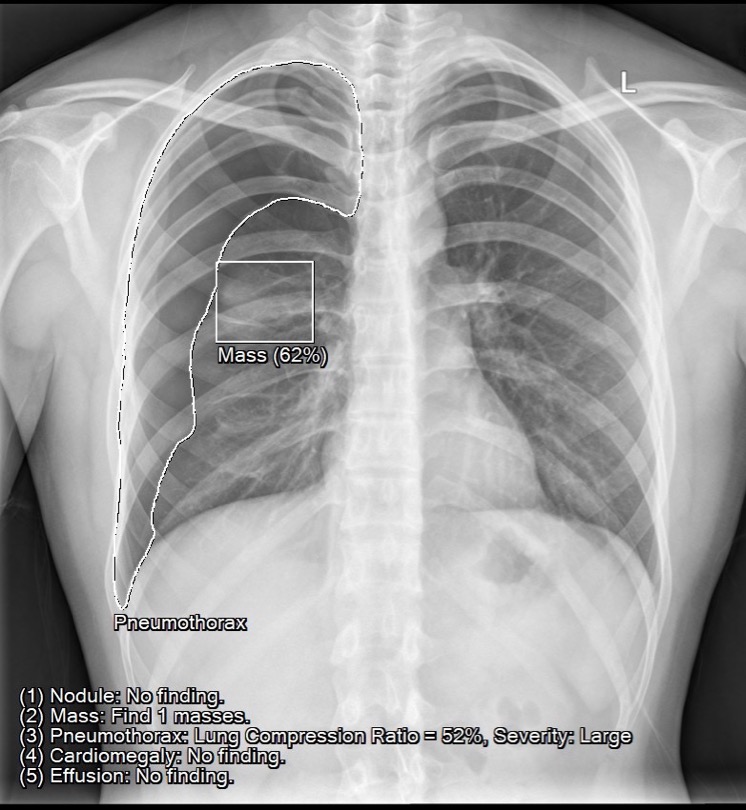

經(jīng)過AIIE推理計算后,整合后的PACS系統(tǒng)會通過病例列表顯示出病癥的嚴(yán)重程度,比如氣胸、大面積胸腔積液會在系統(tǒng)中被標(biāo)注為危急,而中小型氣胸、結(jié)節(jié)腫塊、心臟肥大、主動脈弓鈣化等其它陽性病癥就被標(biāo)注為優(yōu)先狀態(tài),這樣醫(yī)師可以第一時間處理最需要醫(yī)療救助的危重病患。這一功能,無論是在醫(yī)師日常診斷,還是遠(yuǎn)程會診探討說明病情等場景都會起到很好的輔助作用。

1. 腫塊自動檢測與定位。

2. 氣胸自動檢測與定位,同時進(jìn)行肺壓縮比計算與分級。

可調(diào)整閾值:預(yù)設(shè)Compression Ratio大于40%,即算嚴(yán)重。